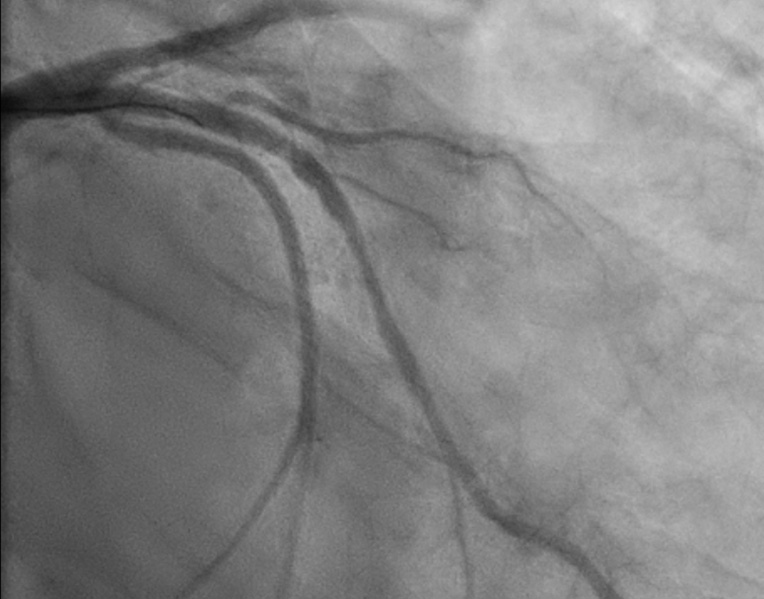

환자는 응급실로 내원해서 위와 같이 thrombotic occlusion이 있었던 분입니다.

PCI는 비교적 간단하게 풍선과 스텐트로만 하였습니다.